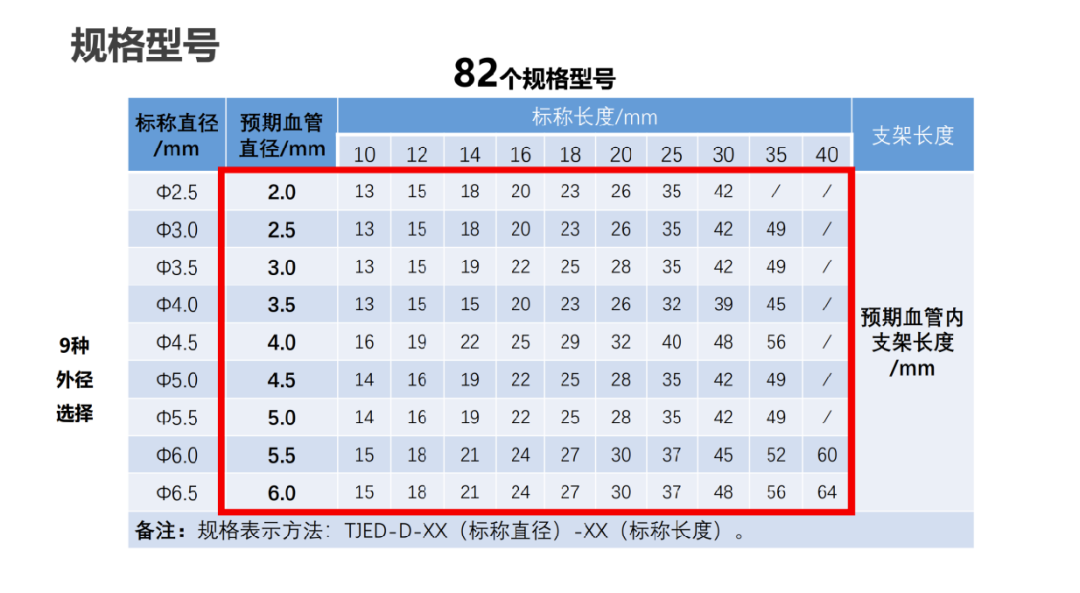

支架规格型号选择关键点

一、大小:

近端血管直径落在标称血管直径与预期血管直径之间;

椎基底动脉或动脉夹层加大+0.5-1.0选择;

二、长度:

三段计算法:远端(延长);动脉瘤颈(标称长度);近端(在标称长度与预期长度之间考量)

远近端锚定长度一般为10-15mm:

1、病变血管直行段较多时,支架预期长度一般选择下限值;

2、病变血管比较迂曲时,支架预期长度可以选择长一些,一般不超过上限值。